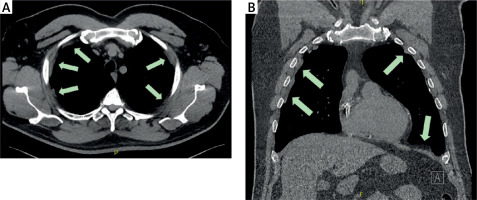

Figure 1

Computed tomography (CT) scan images showing calcified plaques in the parietal pleura (arrows). A – Transverse plane scan of the thoracic cavity. B – Coronal reconstruction highlighting the distribution of pleural plaques